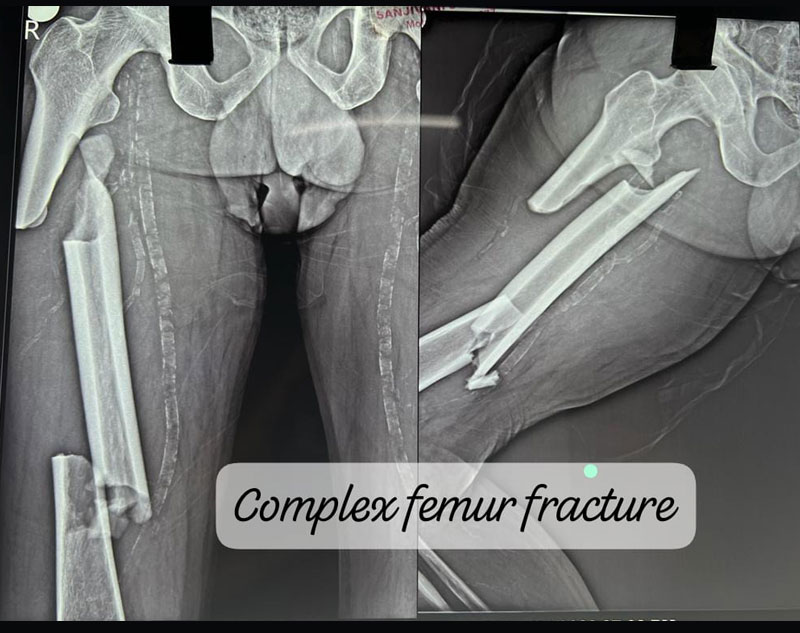

Complex Trauma in orthopedics refers to severe injuries involving multiple or complicated fractures, often combined with soft tissue damage.

These injuries may involve:

Treatment for complex trauma requires a multidisciplinary approach, including surgical intervention, internal/external fixation, and sometimes reconstruction of damaged tissues.